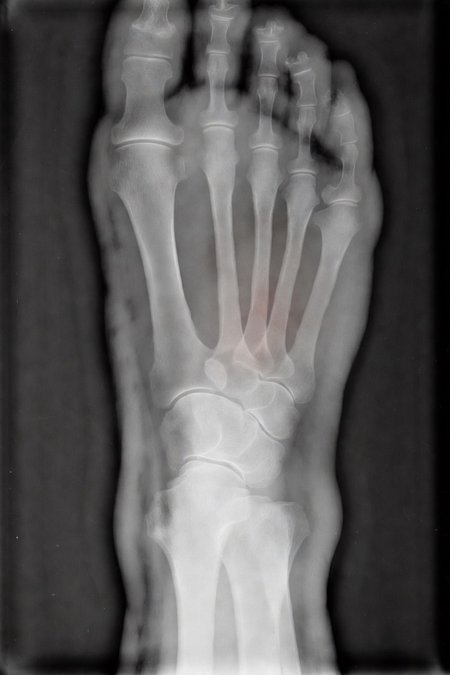

Can a model like Flux Kontext, designed for editing art and photography, be used to work with medical images, for example, with something 'as simple' as red-marking fractures?

The quick answer: it does do something interesting, but it over-scores and is far from reliable as a medical tool. It's a prototype to play with the idea, nothing more.

2. Ask: “Make marks where there is a fracture”.

Good for

AI prototypes and tests on medical imaging.

Eye-catching visualizations of "suspicious" areas in X-rays (experimental and creative art, here's an exotic tool xD)

Didactic/experimental material to play with sensitivity vs false positives.

Not good for:

Diagnose nothing serious.

Replacing a doctor, not even close!

Important

This LoRa is for visual experimentation only. It is not a medical device, it is not reliable and should not be used for clinical diagnosis.

Of course, taking into account that it is open source, fast (25 seconds per analysis) and that it can run on desktop computers, I think it is worth continuing to experiment with this concept in the future... we will see!